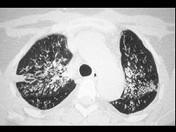

女,35岁,养鸽,咳嗽、咳痰,结合CT,考虑最可能的诊断是 ( )A.肺隐球菌病B.肺转移瘤C.支气管肺炎D.肺结核E.肺泡癌

问题 女,35岁,养鸽,咳嗽、咳痰,结合CT,考虑最可能的诊断是 ( )

选项 A.肺隐球菌病 B.肺转移瘤 C.支气管肺炎 D.肺结核 E.肺泡癌

答案 A